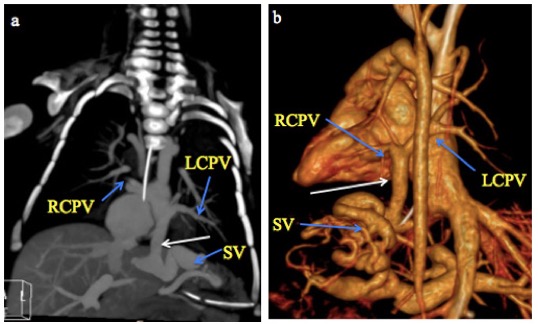

MDCT images of TAPVC are shown in Figures 4 and 5, demonstrating the characteristic drainage patterns of the supracardiac and infracardiac types, respectively.

Fig. 5 A month old male infant with infracardiac total anomalous pulmonary venous connection. a) CT Pulmonary angiography coronal MIP and b) 3-D volume-rendered CT images show the right and left superior and inferior pulmonary veins (RCPV and LCPV) joining to form a vertical vein (white arrow) that descends through the diaphragm and drains into a dilated and tortuous splenic vein (SV).